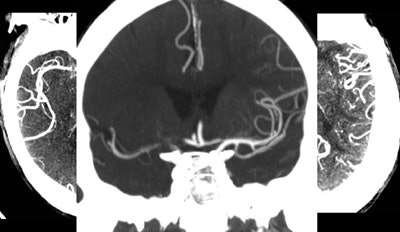

An ischemic stroke patient with a 1-cm hyperdense vessel at CT angiography (not seen) and no visible collateral vessels (above) was visiting a hospital when the stroke occurred. His proximity led to rapid assessment with CT/CTA within 25 minutes, and IV-tPA initiation within an hour of symptom onset. CT showed an M1 vessel occlusion, and CTA revealed a zero collateral pattern, suggesting a large ischemic area. Early treatment was successful, and follow-up CT shows nearly 100% revascularization. Image courtesy of Dr. Michael Lev.Intra-arterial catheter-based reperfusion